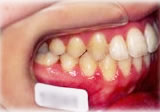

開咬症例

初診時年齢○○歳。前歯部での咬合不全を主訴に来院。

骨格性開咬と診断し、外科的処置を併用して治療。

治療前 治療後

左側面 左側面 左側面